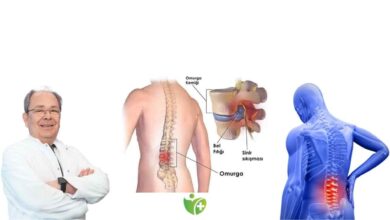

En sık görülen sinir sıkışmasının karpal tünel sendromu adıyla bilinen ve el bileğinde median sinirin sıkışmasıyla ortaya çıkan klinik tablo olduğunu paylaşan Prof. Dr. Selçuk Göçmen, “Ayrıca, dirseğimizin dış kısmında ulnar sinirin ve dizimizin yan-dış kısmındaki peronel sinirin sıkışmasına ait klinik tabloları da sık görülen sinir sıkışmaları arasında sayabiliriz” şeklinde konuştu. Sinir sıkışmasının nedenleri arasında diyabet, romatizmal hastalıklar, tiroit hastalıkları, menopoz, oturuş ve duruş bozuklukları, kırılan ya da yerinden kayan kemikler, hamilelik, obezite, ani kilo kayıpları, tümörler, tekrarlayan yanlış hareketler, otururken ve yatarken yapılan yanlış pozisyonlar sorunun görülme oranını artıran başlıca faktörler olduğunu belirten Anadolu Sağlık Merkezi Beyin ve Sinir Cerrahisi Uzmanı Prof. Dr. Selçuk Göçmen “Cisimlerin elle sıkı ve şiddetli bir şekilde tutulması, bileğin aşırı bükülmesi gibi aktiviteler de benzer şekilde görülme oranlarını yükseltiyor” dedi.

Ağır düzey sinir sıkışmaları cerrahi yöntemlerle tedavi edilebiliyor

Hafif ve orta düzeydeki sinir sıkışmaları için uygulanan konservatif tedavinin sinir üzerindeki baskıyı ortadan kaldırmak için olduğunu, tedavide ayrıca iltihap giderici ilaçların da yazılabildiğini veya kortizon enjeksiyonlarının yapılabildiğini belirten Prof. Dr. Selçuk Göçmen, “Eğer hastalar istirahat, rehabilitasyon veya diğer tedavilerle iyileşmezse ve tetkiklerde ağır düzeyde sinir sıkışıklığı saptanmışsa cerrahi tedavi yapılması uygun olabilir. Açık cerrahide, bir kesi yapılarak sinir üzerinde bası oluşturan bantlar kesilir ve sinir serbestleştirilir. Endoskopik yöntemde ise, küçük bir kesi yapılarak endoskopik kamerayla bant içeriden kesilir ve bası kaldırılır. Her iki yöntem de genellikle lokal anestezi eşliğinde yapılır. Ameliyat yaklaşık 30 dakika sürer ve hastaya günübirlik yatış yapılabilir” açıklamasında bulundu.